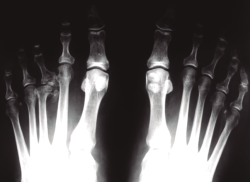

Las necrosis asépticas aparecen en aquellos puntos de nuestro aparato locomotor sometidos a importantes solicitaciones mecánicas, sea por microtraumatismos o por sobrecarga estructural. En el caso de la enfermedad de Freiberg, diversos autores(2,10,11,12) apoyan esta teoría que nosotros compartimos, ya que hemos visto muchos casos de afectación del segundo metatarsiano acompañando una insuficiencia del primer radio, sea por un hallux valgus o por un primer metatarsiano corto (Figura 2). En nuestro estudio a largo plazo sobre la enfermedad de Freiberg(13), sobre 16 pies operados, 12 padecían la sobrecarga mecánica.

Figura 2. Etiología mecánica. La enfermedad de Freiberg se asocia frecuentemente a una insuficiencia del primer radio.